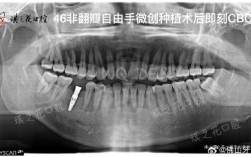

种牙CT测量数据是种植手术前评估口腔条件、制定精准方案的核心依据,其准确性直接关系到种植体的初期稳定性、长期存活率及患者术后体验,与传统二维X光片相比,CT三维成像能清晰显示牙槽骨的立体结构、重要解剖位置及骨密度分布,为医生提供全面的数据支...